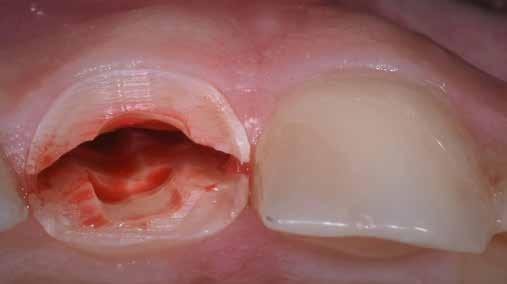

A korai harmicas éveiben járó hölgy rendelőnkbe érkezésének oka a jobb felső nagymetsző fog bizonytalan érzkenysége, elmondása alapján gyermekkorában trauma érte a felső frontrégiót. A frakturált klinikai koronákat kompozittöméssel helyreállították, egyéb kezelést akkor nem tartottak szükségesnek. Az utóbbi hónapokban tapasztalt érzékenység miatt kereste fel rendelőnket. A klinikai vizsgálat (1. és 2. kép) és a CBCT felvétel (3. kép) alapján diagnosztizált külső gyökérreszorpció megoldására a fog eltávolítását, implantátum

behelyezését, majd csavarozott rögzítésű, cirkónium-dioxid vázas, kerámialeplezésű korona készítését terveztük [1., 5., 6., 8.].

A socket-shield technika lényege az azonnali implantációt megelőző részleges fogeltávolítás. Dekoronálást követően a megmaradt gyökér több darabban kerül eltávolításra, azonban a

bukkális 1. kép: Kiindulási állapot, 2020. január. 3. kép: Kiindulási CBCT felvétel. 2. kép: Kiindulási állapot a palatinális oldal felől.

falat mint „pajzsot”, meg kell őrizni, ezzel megelőzhető a bukkális csontfal egyébként fiziológiás reszorpciója (4. és 5. kép). A sebészi technika különös körültekintést követel meg, nehogy a bukkális „gyökérpajzs” megmozduljon, ezzel a bukkális oldalon megmaradt periodontális ligamentumok sérülését kockáztatnánk, amely az esetenként